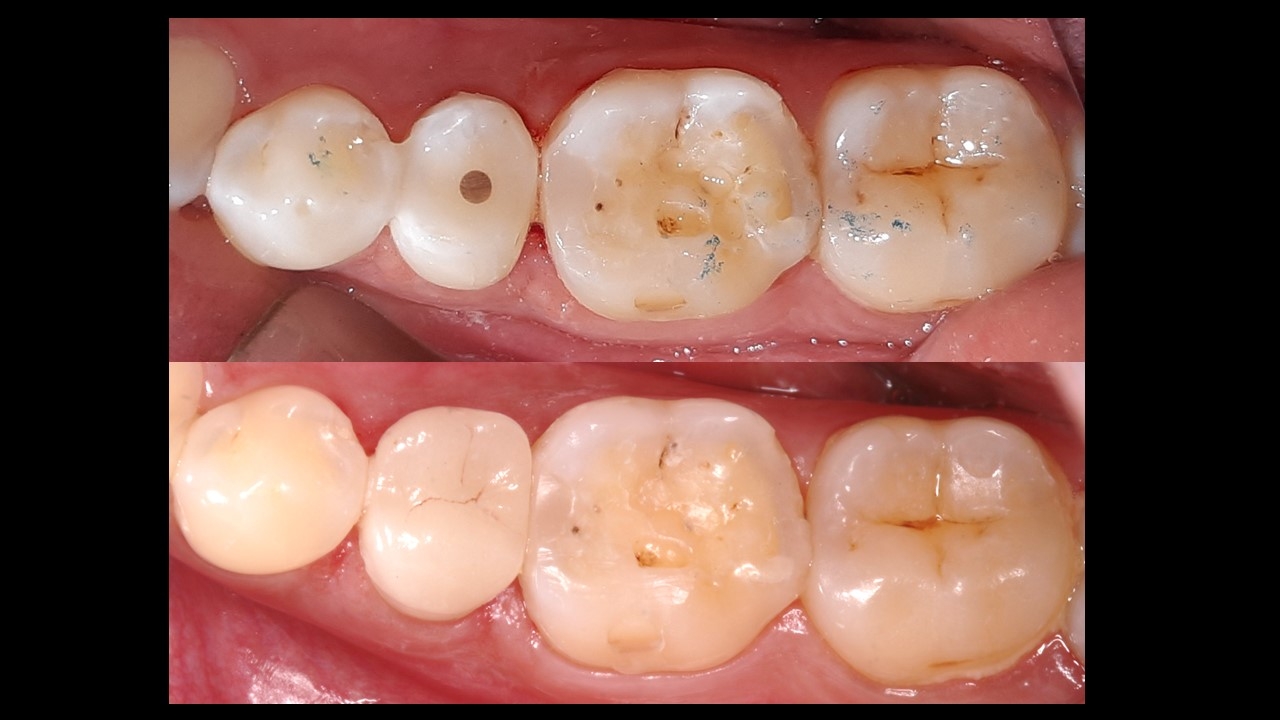

Treatment plan:

Root canal therapy (RCT)in lower right 2nd premolar and lower left 1st molar.

Filling in lower right 1st molar.

Post (fiber) and core , Emax onlay